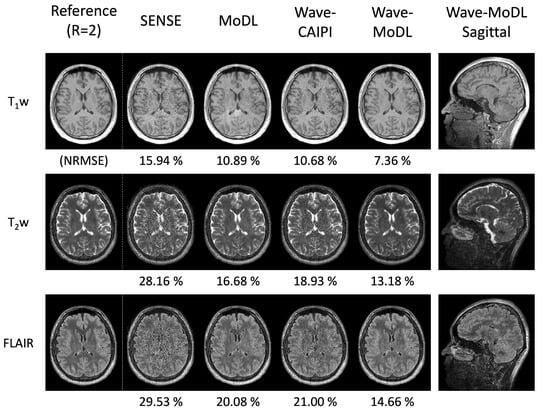

4.2. MEMPRAGE at R = 3 × 3

4.3. 3D-QALAS at R = 4 × 3